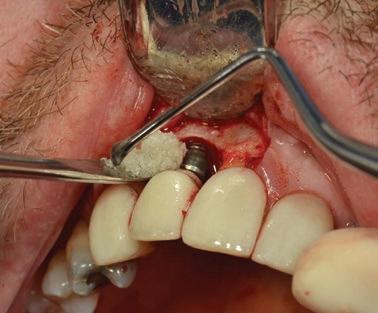

La gestion de l’alvéole post-extraction constitue un défi fréquent en pratique clinique. Lorsqu’un traitement implantaire est envisagé, le contrôle de la résorption osseuse verticale et horizontale devient essentiel afin de préserver les conditions idéales pour un futur positionnement implantaire.

L’objectif de ce module est de permettre une approche rigoureuse de la préservation alvéolaire, en vue d’optimiser le positionnement tridimensionnel de l’implant et de faciliter l’intégration fonctionnelle et esthétique de la restauration prothétique.

Maîtriser les techniques d’extraction atraumatique

Sélectionner les biomatériaux appropriés (substituts osseux, membranes) et les techniques de suture

Pratiquer les techniques de préservation alvéolaire en atelier